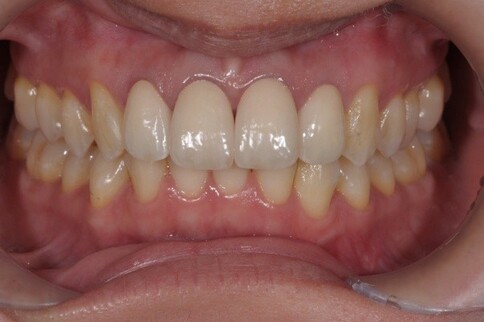

✨ 三、 四至六顆:微笑曲線重塑

Case 7:外突內收打造理想笑線,提亮色階。